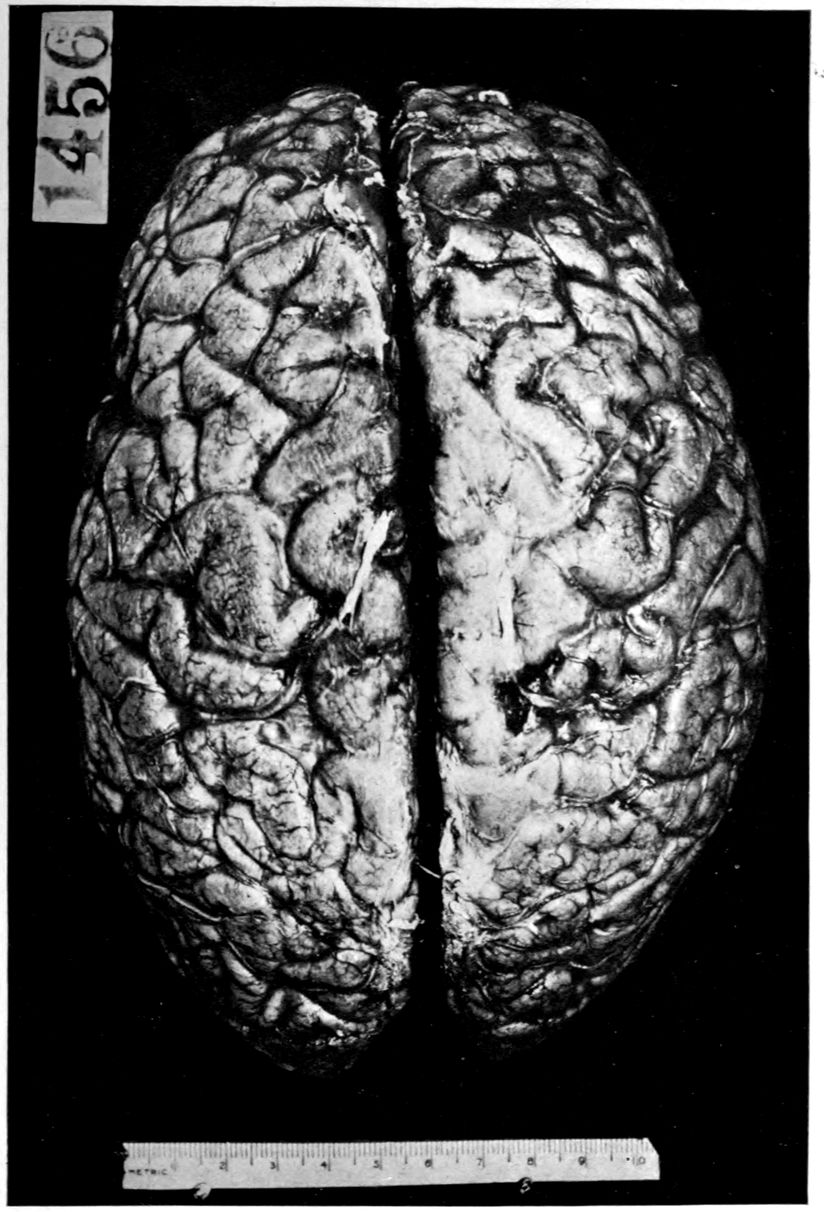

Brain weight, 1265 grams. Consistence somewhat increased throughout and somewhat evenly increased. The prefrontal region shows the maximal increase of consistence but the remainder of the frontal region and corresponding occipital region are much firmer than normal. The two superior temporal gyri appear to be firmer than adjacent gyri and are possibly slightly diminished in superficial diameter. The hippocampal gyri are fairly firm. The substance on section is a trifle more moist than normal. The gray and white matter cut quite evenly. Diminution in depth of gray matter, if existent, could not be demonstrated. The ventricles show a moderate sanding throughout, best marked in the fourth ventricle. The basal ganglia are not remarkable except for the development of numerous dilated perivascular spaces about the lenticulostriate vessels. The pons is atrophic, but more so on the right side. The pons, like the prefrontal cortex, shows on section a distinct increase of consistence immediately beneath the pia mater. The white bands of the pons on section are distinctly firmer than the intervening substance. The olives are of equal consistence. Weight of cerebellum, pons, and medulla, 155 grams. The cerebellum shows an obvious atrophic and gliotic process of a symmetrical character. The superior surface, including both vermis and hemispheres, shows a consistence above normal and general reduction of the depth measured from the white matter. The reduction in depth gives rise to a visible depression as compared with tissue posterior to the postclival sulci. The lobus cacuminis, though slightly raised from the surrounding lobes, is equally firm, if not firmer. The superior and inferior surfaces show practically an equal increase of consistence. The dentate nuclei are not especially increased in consistence. The flocculi are reduced in size about one-third.

The calvarium was dense and the dura mater thick and adherent. There was a chronic leptomeningitis, which, however, was rather unusual in being most marked in the posterior cisterna and along the sulci of the cerebellar hemispheres. There was a general cerebral sclerosis, with a question of atrophy of the superior temporal gyri (suggesting the so-called Lissauer’s paresis). There was a marked cerebellar sclerosis with a consequent sclerosis (grossly palpable) of the commissural fibres of the pons. There was a generalized slight spinal sclerosis. As a fair sample of the variety of head findings in paretic neurosyphilis, the details of the head examination are presented.

Brain: Weight 965 grams. The sulcation is roughly symmetrical except in the occipital poles where there is unusually rich and complex but shallow sulcation. The cortical substance is everywhere firmer than normal, but the sulci fail to flare notably. In a few places there is a focal increase of consistence of still greater degree with apparent local hypertrophy (or gliosis with increase of substance). These foci are in the right second temporal gyrus (3 cm. in diameter) and in the left first temporal gyrus (of same size but somewhat less firm) and are of a whitish, waxen appearance, being visible several feet away by reason of their color and apparent encroachment upon the adjacent sulci. The foci are sharply limited by the sulci laterally, but pale out gradually before and behind.